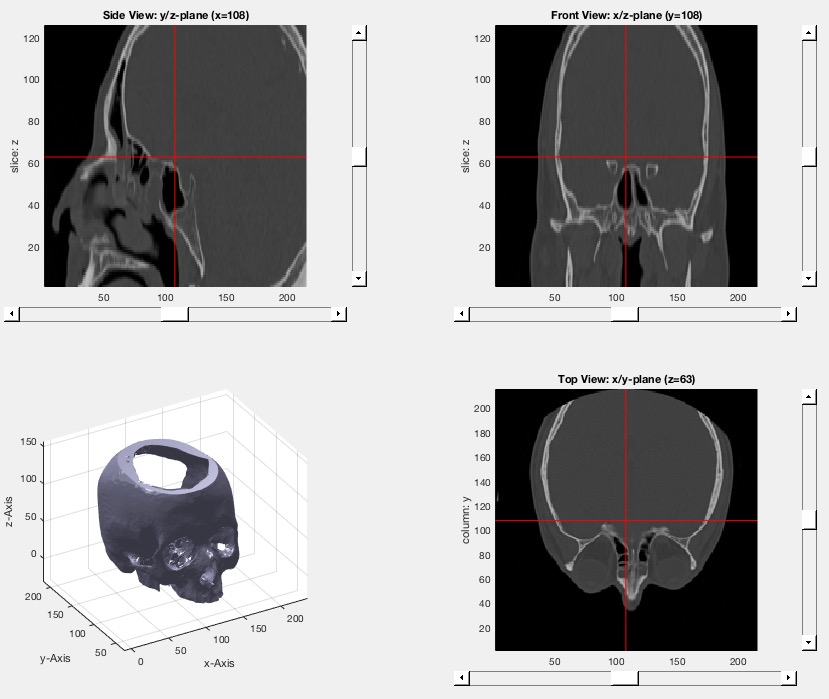

VMplot (IM,p,SG)- plots a 3D volumetric matrix in 2x2 view |

| % VMplot (IM,p,SG) - plots a 3D volumetric matrix in 2x2 view % (by Tim Lueth, NAV-Lib, 2017-FEB-23 as class: VISUALIZATION) % % Based on VMplot_2012. Does support sliders for scrolling, and 3D % visualization; % % Global VMplotPos specifies the cross hair position % (Status of: 2017-04-02) % % See also: VMintensityscale, VMimage, VMimrot90, VMmontage, VMpseudo3D, % VMreaddicom, VMreaddicomdir, VMuidicom, VMgetSubplot, VMginput % % VMplot([IM,p,SG]) % === INPUT PARAMETERS === % IM: 3D Matrix % p: optional point of interest; default is center % SG: optional solid of the Volume; % % EXAMPLE: % [V,vs]=VMreaddicomdir('/Volumes/LUETH-WIN/WIN AIM Matlab % Libraries/VLFL-Lib/AIM_DICOMFILES'); % [V,vs]=VMresize(V,vs,vs); % SG=SGofVMdelaunay(V>1400,vs); % VMplot(V,'',SG) % % |

exp_2017_02_21- EXPERIMENT SCRIPT to load and precalcuate a skull bone surface model |

| % exp_2017_02_21 - EXPERIMENT SCRIPT to load and precalcuate a skull bone surface model % (by Tim Lueth, VLFL-Lib, 2017-FEB-21 as class: EXPERIMENTS) % % exp_2017_02_21 % |